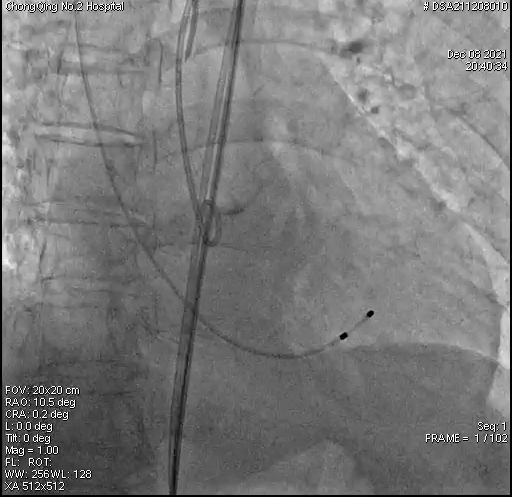

手术过程:

2、AL2导管配合直头超滑导丝跨瓣;

3、22mm球囊预扩张,腰征明显;

4、27mm VitaFlow Liberty™瓣膜定位,零位释放;

5、瓣膜释放3/4,造影显示冠脉良好,瓣膜电动释放稳定,无位移;

6、在影像团队密切配合下,调整角度,短轴视角再次造影确认瓣膜植入深度可,超声确认瓣架深度与左冠距离可;